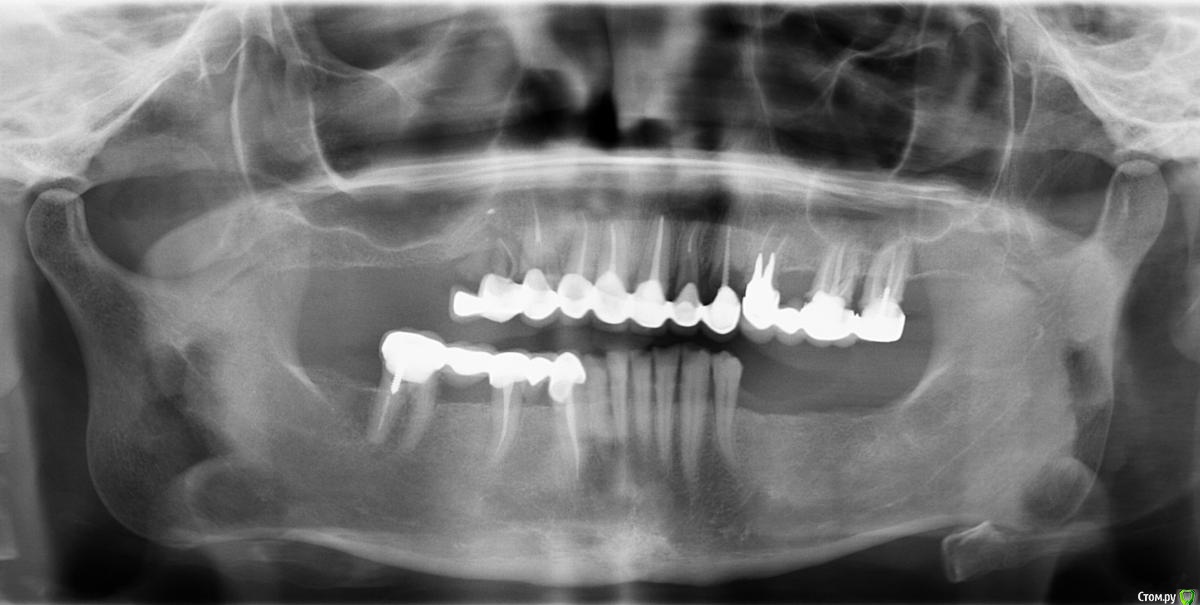

Talita Опубликовано 24 июля, 2019 Автор Поделиться Опубликовано 24 июля, 2019 дальнейшее обсуждение без снимков будет закрыто.Я выложила в первом сообщении ссылку на архив с КТ ( “DICOM” там нет). Панорамный снимок прикрепляю. Ссылка на комментарий